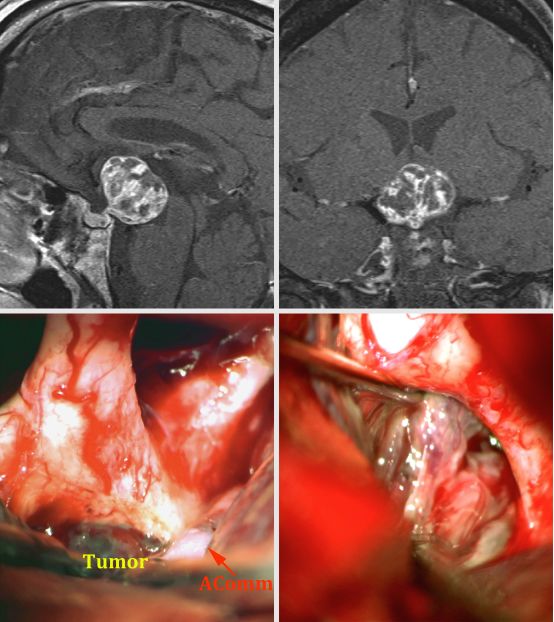

图1. 显示两个不同大小和形态的颅咽管瘤患者的影像。在上排的影像显示一个大的稍微实性的颅咽管瘤,能够经额下入路通过终板暴露。另一方面,在中排和低排的影像显示一个部分囊实性肿瘤,适合经鼻入路。注意右侧下面的影像为CT上发现的结节性钙化。两个肿瘤对垂体柄的明显包绕使得在切除过程中试图保留垂体柄几乎不可能。

图7. 一个视交叉前方的囊性颅咽管瘤(第一排影像)经翼点入路切除。同侧视神经通过引流囊肿减压,肿瘤囊壁被切除(中排影像)。从下丘脑锐性分离肿瘤结节(左下排影像)。最后切除结果和额下手术路径如图显示。垂体柄(箭头)保持完整(右下排影像)。